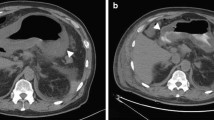

A case of phlegmonous gastritis, diagnosed for the first time without laparotomy and with spontaneous recovery, is described. The only procedure allowing nonsurgical diagnosis of this disease is endoscopic snare (“jumbo”) biopsy of the giant folds in the diseased parts of the stomach. Snare biopsy includes submucosal tissue which is the main site of histological changes in phlegmonous gastritis.